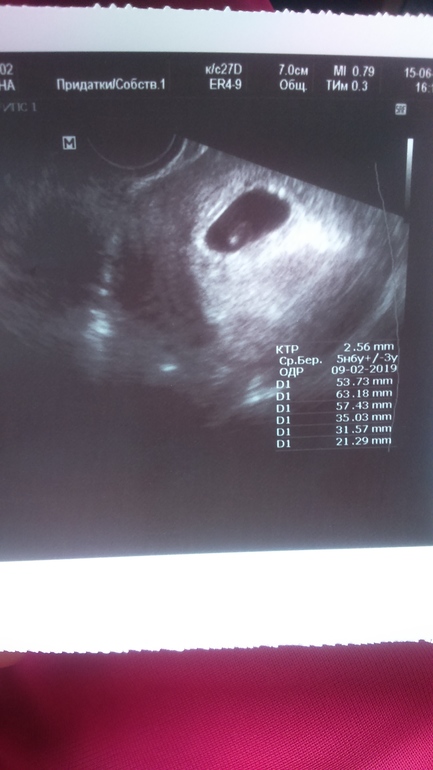

БеременностьДо сегодняшнего дня все было спокойно и я никому кроме мужа о Б не рассказывала, хотя спрашивали многие, но я отнекивалась. И вот сегодня на работе ген директор сказал, чтоб я или по сменам выходила или увольнялась, тк я единственный мастер на заводе, который работает с 8 до 17 и его это не устраивает. Пришлось сказать что я Б. Потом после нервов разболелся живот и наша медсестра договорилась с врачом, чтоб меня сегодня приняли. меня отпустили с работы и я поехала к врачу. Она сначала по животу смотрела, увидела пл. яйцо и ж м, потом внутренне нашла эмбриончика 2,55мм и сб+ жт в правом я 21мм . Срок 5н6дн поставила, сказала что все хорошо с малышиком, выписала направление на свертываемость крови и на прогестерон, чтоб посмотреть нужна ли поддержка. А в справке для директора написала, что угроза есть, чтоб наверняка не поставили в ночные смены. После узи сразу отлегло и все проблемы с работой ушли на второй план. Главное, что все хорошо с малявочка, остальное мелочи жизни, а еще нам фоточку дали)))